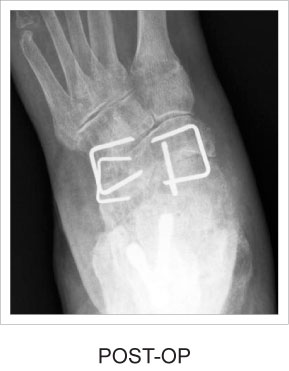

Grapas de Nitinol para Pie

Las grapas de Nitinol superelásticas ofrecen una compresión continua y dinámica durante la curación.

• Se utiliza para fracturas, osteotomías y fusiones de huesos pequeños en la mano y el pie.